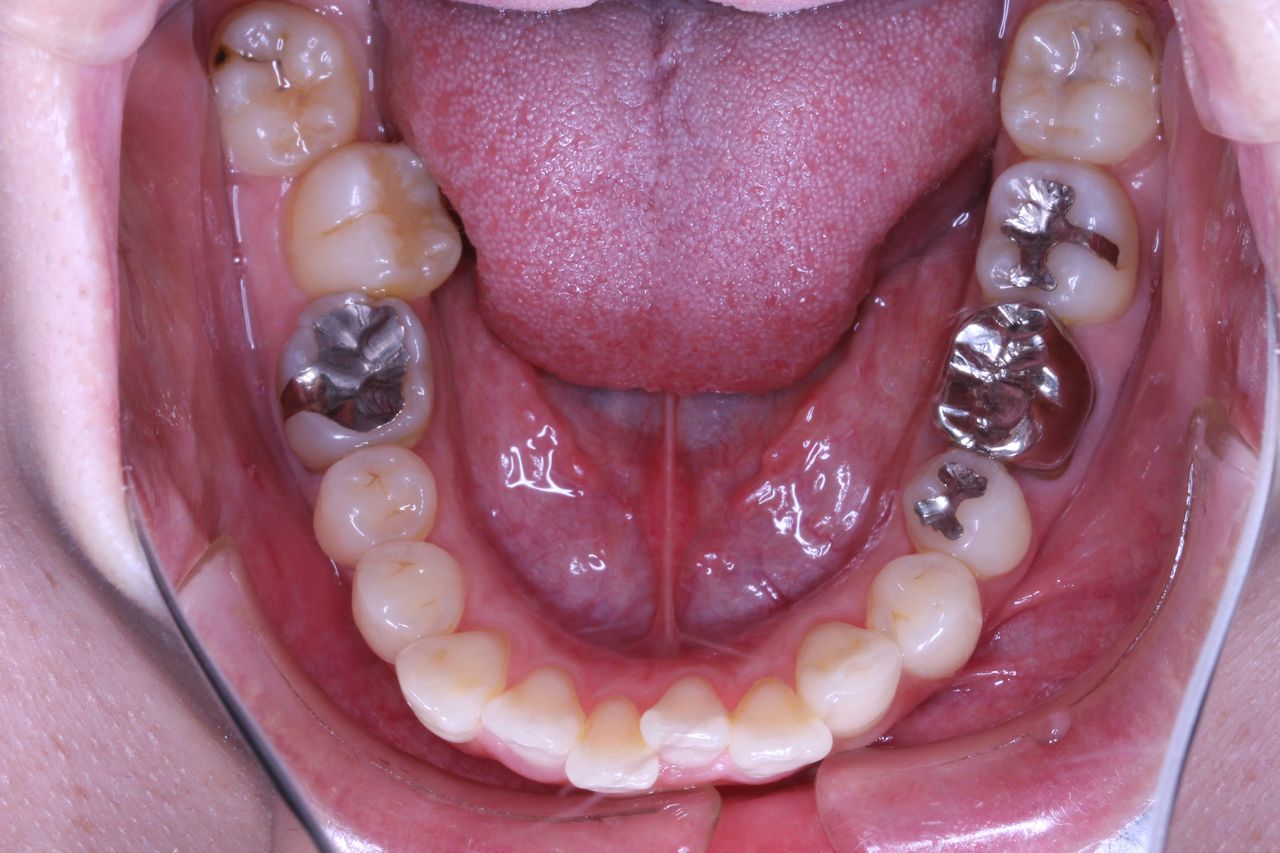

少し経過が進みました